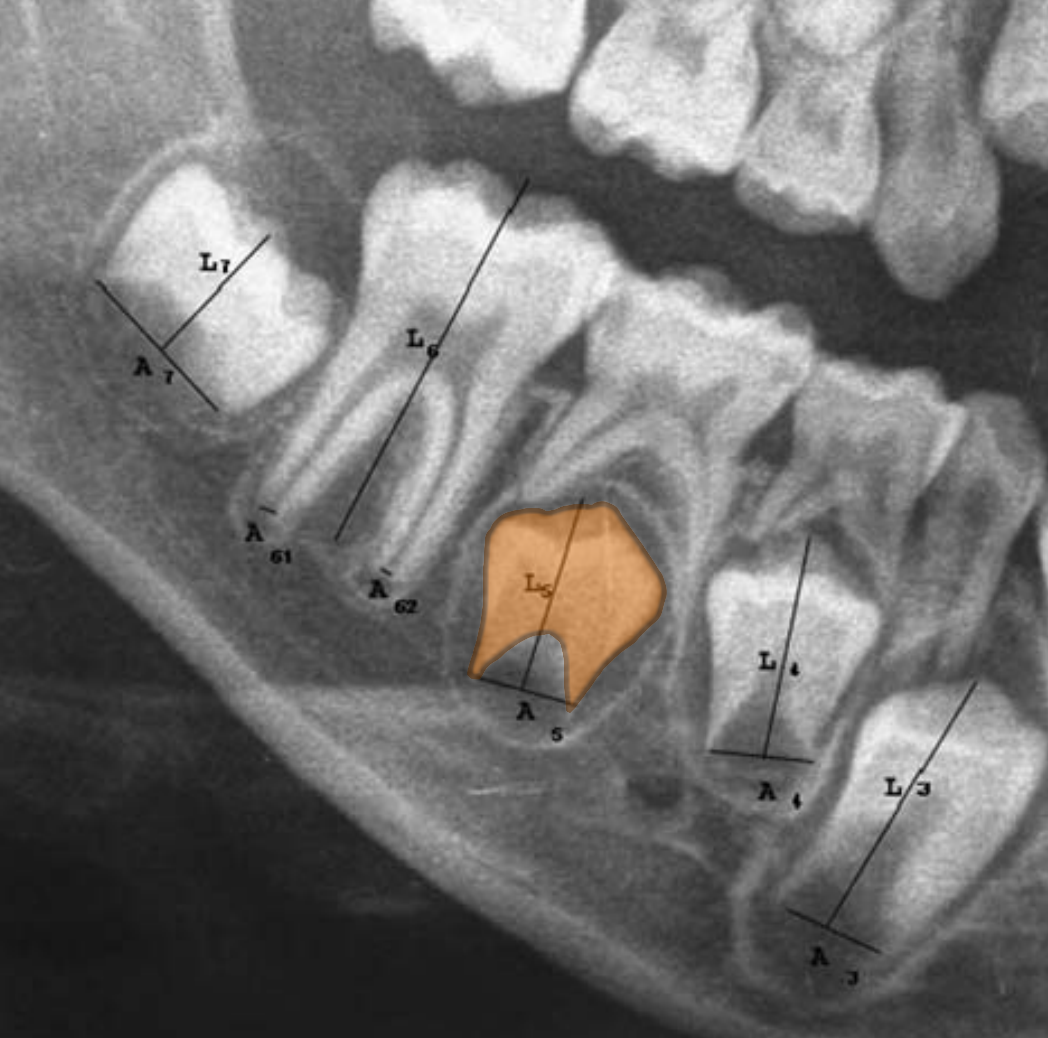

To provide a more comprehensive visual explanation (dental images), dental experts recommended the development of a textual explanation (narratives) that is as straightforward and intuitive as possible, similar to that associated with the well-known transparent estimation method proposed by Cameriere et al. (2006). This method is based on tooth measurements in the fourth quadrant of the dentition, as illustrated in Figure 2. It is easy to explain reasonably and understandably both the application of the method and the influence of the patient’s dental characteristics on the estimation of age, which is done by the following linear regression model:

Refer to caption

Figure 2: Measurements used to compute CSM(4i)=Ai/LiCSM(4i)=A_{i}/L_{i}, i{1,,7}i\in\{1,...,7\} by Cameriere et al. (2006). AiA_{i} correspond to the apex openness, while LiL_{i} correspond to each tooth height. The image shows the mandibular right quadrant of a patient’s dentition, with tooth 45 (second premolar) highlighted